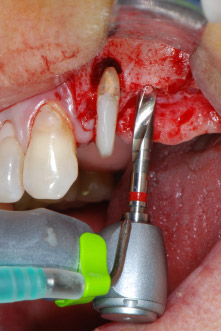

Fig. 8: Rotary preparation of the implant bed short of the floor of the maxillary sinus at position 25, carried out with an updated implant motor.

Implant beds were prepared at sites 25 and 26 with rotary instruments, used in a contra-angle handpiece with a 20 : 1 transmission ratio with an updated powerful implant motor (Implantmed, W&H) (Fig. 8).